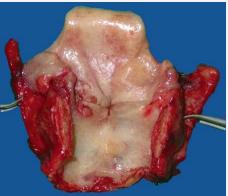

Endolaryngeal resection, control of margins and assessment of intact thyroid ala with subperichondral dissection, in the necessity of frozen section, is performed in Figures (5a,b)). Specimen of the HVL procedure contains supraglottis (epiglottis with PES), and lesion side of glottis (false and true vocal cord, arytenoid with PGS and subglottis up to cricotracheal membrane) (Figures 6a,b).

Figure 6 (a) En block resection of transglottic tumor, (b) Specimen of the HVL resection.

Figure 6: (a) En block resection of transglottic tumor, (b) Specimen of the HVL resection.